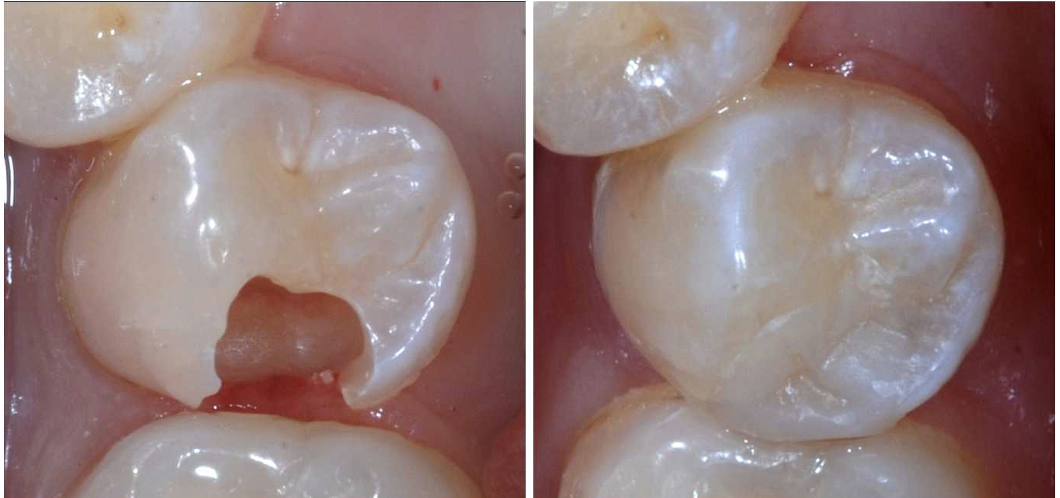

<p>classify this type of restoration</p>

classify this type of restoration

intracoronal fixed direct restoration